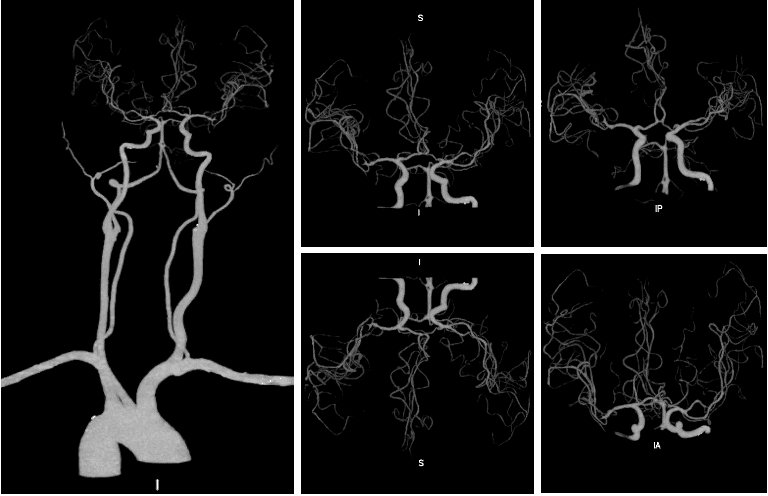

头颈CTA(2023-09-16)示右侧颈内动脉C1段管壁混合斑块,管腔轻度狭窄;右侧大脑前动脉A2段管腔非钙化斑块,管腔轻度狭窄。